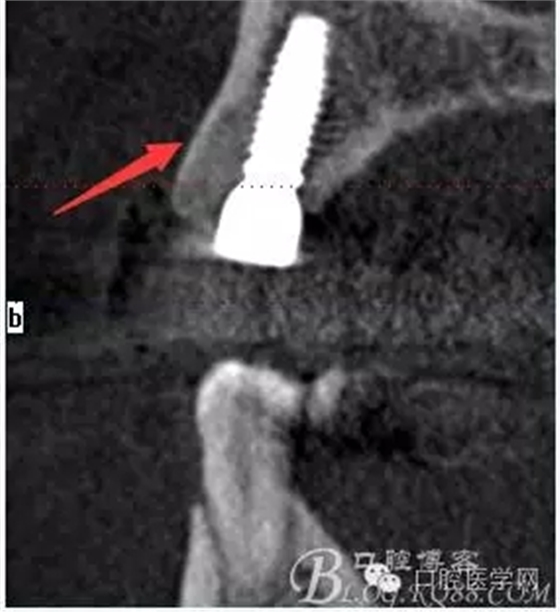

術(shù)后片顯示方向非常可以

頰顎向的方向也很理想 箭頭所示 空間填滿了自體骨